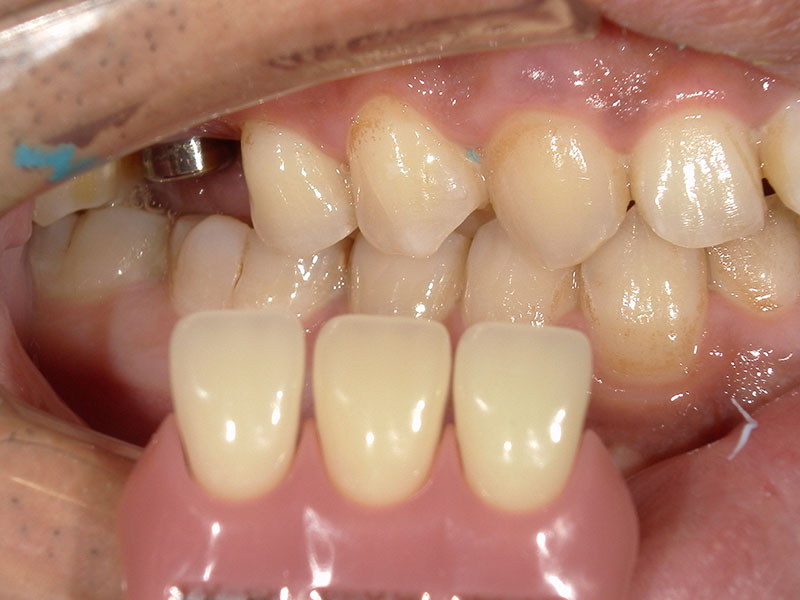

インプラント上部構造装着

インプラントの上部構造を装着しました。インプラント部の清掃性を考え、小臼歯が2つ並んだような形態にしました。こちらの形態の方が歯間ブラシが通しやすくインプラントが長持ちします。